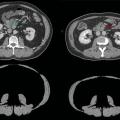

Les objectifs visés sont importants, consistant à optimiser la prédiction de la mortalité, de la morbidité, parfois l’apparition de lésions cancéreuses.2 De manière schématique, l’imagerie d’opportunité concerne principalement aujourd’hui les marqueurs de la maladie cardiovasculaire, les marqueurs d’ostéoporose et les marqueurs liés à la sarcopénie (figure). L’évaluation de la masse musculaire globale et l’identification «  opportune  » sur le scanner d’une potentielle sarcopénie permettent de prédire des évolutions péjoratives, notamment en cancérologie, indépendamment des traitements conduits.4,5 Dans une étude parue en 2023, les équipes de Pickhardt et al. ont rapporté leur expérience sur l’analyse rétrospective de 9 223 dossiers de patients ayant bénéficié d’un scanner abdominal et de l’extraction opportune de biomarqueurs quantitatifs (quantification des muscles en projection de L3, quantification de la graisse abdominale en L3 et quantification automatique du score de calcification de l’aorte abdominale).6 L’atténuation musculaire en L3 et la quantification des calcifications aortiques présentaient les meilleures performances pour prédire la survenue d’un décès dans les dix ans, avec un AUC (area under the curve ou aire sous la courbe) de 0,76 chez les hommes et de 0,72 chez les femmes, concernant l’atténuation musculaire.6